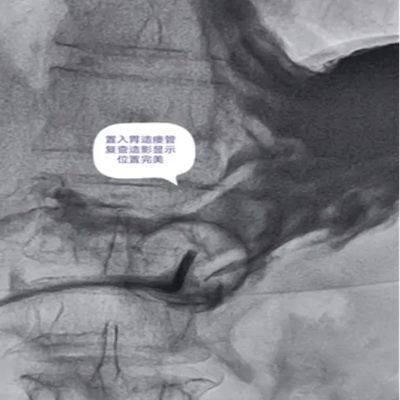

DSA引导下经皮胃造瘘术,是在数字减影血管造影(DSA)这个“透视眼”的实时可视化导航下,于患者腹壁上建立一个仅 3-5毫米 的微小穿刺点。通过这个“针眼”,医生精准地将一根营养管直接置入胃部,建立起一条直达的营养通道。

整个过程就像一次精准的“导航穿刺”,全程操作便捷、创伤小,却能完美替代传统的鼻饲管,为患者提供长期、稳定、安全的营养支持。

DSA影像全程清晰可视化,可精准避开血管、脏器等重要组织,穿刺定位误差小;穿刺创口仅3-5mm,出血量少,术后反流、误吸、肺炎等并发症发生率低于5%,术后1-2天即可正常喂养,恢复速度快。

医院临床实践中就有典型案例:一名65岁食道癌伴淋巴结转移患者,因食道狭窄无法插入胃镜,且体质虚弱难以耐受全麻手术,团队借助DSA精准导航,仅用10分钟便完成手术,局部麻醉下患者全程无明显不适,术后1天即可通过造瘘管补充营养,为后续抗肿瘤治疗顺利开展奠定了坚实基础。